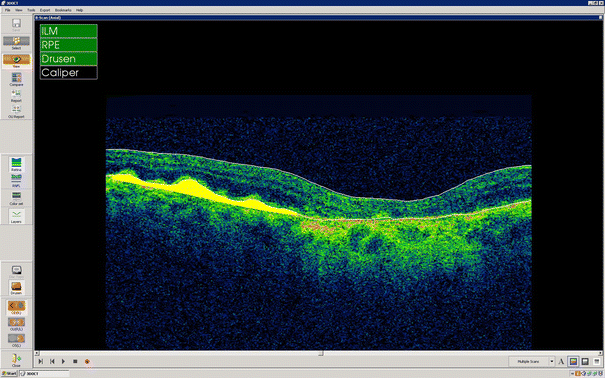

Optical coherence tomography (OCT) B-scan (3D OCT-2000, Topcon, Japan) obtained from a patient with large numbers of drusen. Automated segmentation of the retinal pigment epithelium (RPE) facilitates quantitative analyses of drusen and pigment epithelium detachment (PED)

Detailed quantitative analyses of drusen obtaining using optical coherence tomography (OCT) in a patient with dry age-related macular degeneration (AMD) (3D OCT-2000, Topcon, Japan)